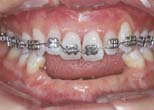

Ant. space closure or redistribution without movement of post. teeth